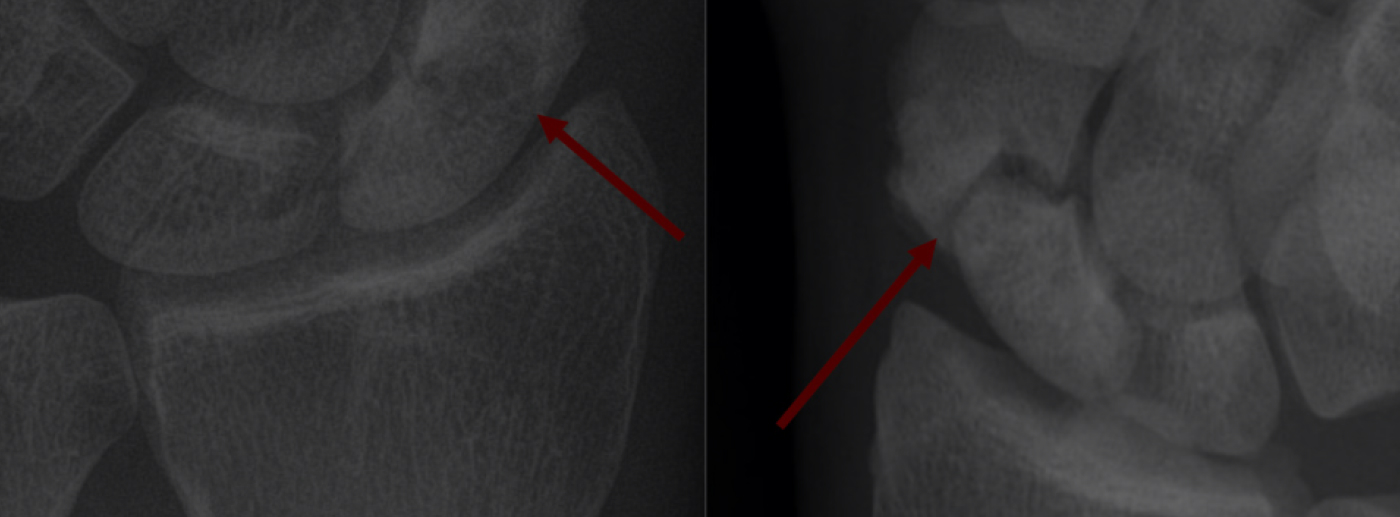

정확한 골절의 위치, 각도, 회전 방향까지 분석해 수술계획을 수립하고,

• 3D 기반 맞춤 수술

Planning

• 02. 최신형 3d 기반 골절 진단 및 수술 planning